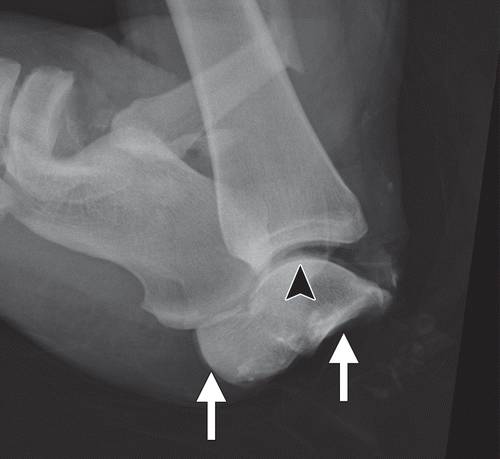

这种损伤必须与三角骨 - 一个附件后骨小梁区分开来。 在放射照相术中,后过程的断裂显示不规则的边缘(图13),而三角骨是圆形或椭圆形,具有光滑的皮质边缘(图14)。 双侧X线照片的价值有限,因为据报道三分之二的病例是双侧的(32)。 如果射线照片不确定,应进行CT。

图13b后突骨折。 (a)右足的外侧X光片显示在距骨后方的小骨质碎片(箭头)。 (b)右脚的轴向CT图像显示后路过程骨折(箭头)以及粉碎的程度和程度。

图14 三角骨。 踝部的侧面X线片显示在距骨后方的椭圆形皮质骨化(箭头)。